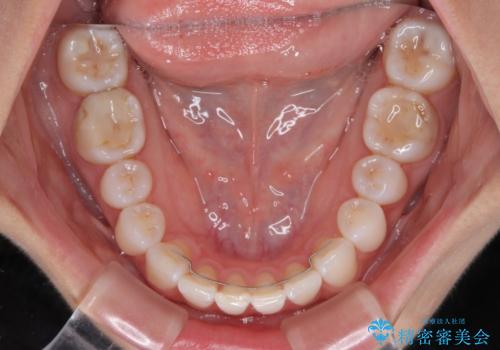

【モニター】前歯のデコボコと小さい前歯 インビザライン矯正とオールセラミッククラウン補綴治療

- 前歯の歯並びと生えてきたときから小さい前歯を気にして来院された患者様です。

上下前歯の歯列不正はインビザラインにより整え、その後に、矮小歯の前歯をオーダーメイドタイプのオールセラミッククラウンにて補綴治療することとしました。

セラミッククラウンにて大きさを変更することを前提に矯正治療を開始したため、大変満足のいく仕上がりとなりました。